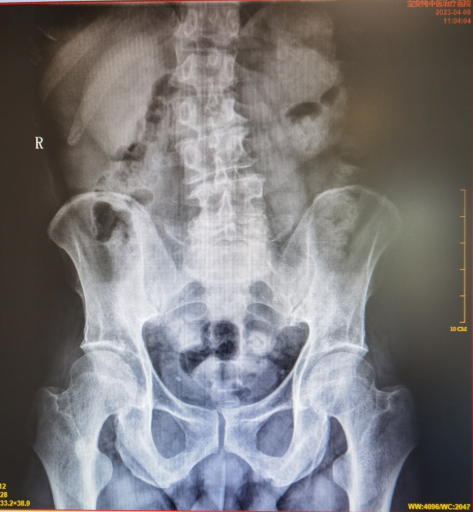

2023-04-08我院腰椎、骨盆正侧位片:

1、腰椎退行性变;腰5椎体向前I度滑脱,建议腰椎双斜位检查。

2、骨盆旋转、后倾。

该患者腰椎侧位片可见腰椎的横径变大,可判断为先天性椎弓峡部裂导致的真性腰椎滑脱,而经过中医保守(手法理筋、针灸)治疗后解除了大部分神经压迫症状,基本恢复了正常的日常生活。因此,可暂不考虑手术治疗。